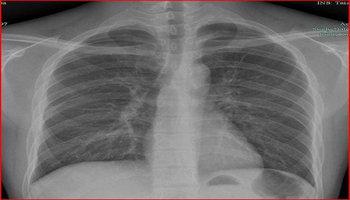

肺部感染胸片,肺部感染片子

5种肺部感染的影像学鉴别(多图)

胸片显示特征性的双肺上叶纤维化.

基本介绍 x线胸片的特点x线胸片能清晰地记录肺部的胸片大体病变,如